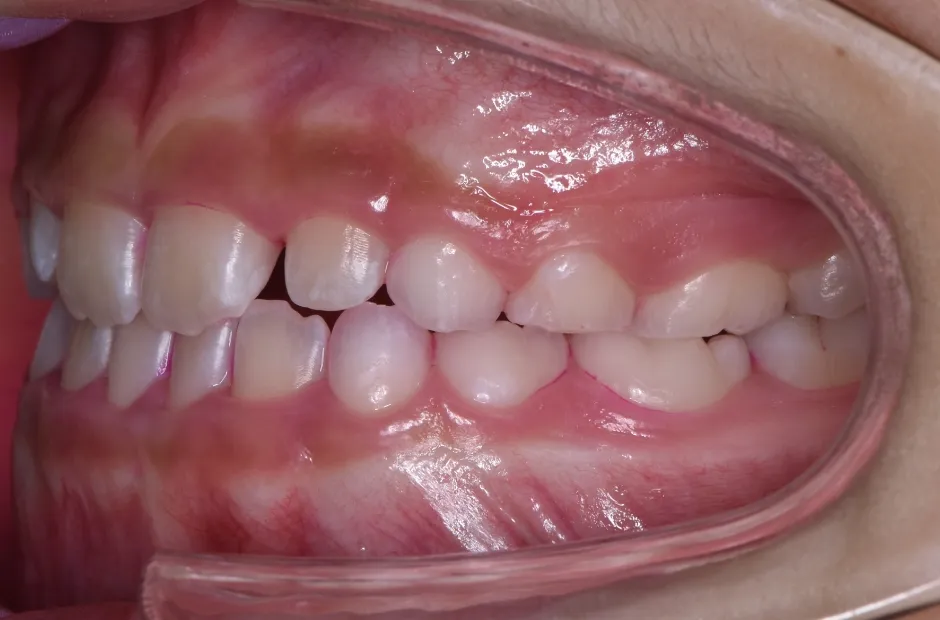

前歯部反対咬合

| 診断名・主訴 | 前歯部反対咬合 |

|---|---|

| 年齢・性別 | 14歳・男性 |

| 治療期間・回数 | 1年2か月 |

| 治療に用いた主な装置 | ブラケット矯正 |

| 抜歯部位 | なし |

| 治療費 | 60万円(税抜) |

| リスク・副作用 | 装置による違和感・疼痛・歯肉退縮・歯根吸収・虫歯のリスクなど |

治療前

治療後